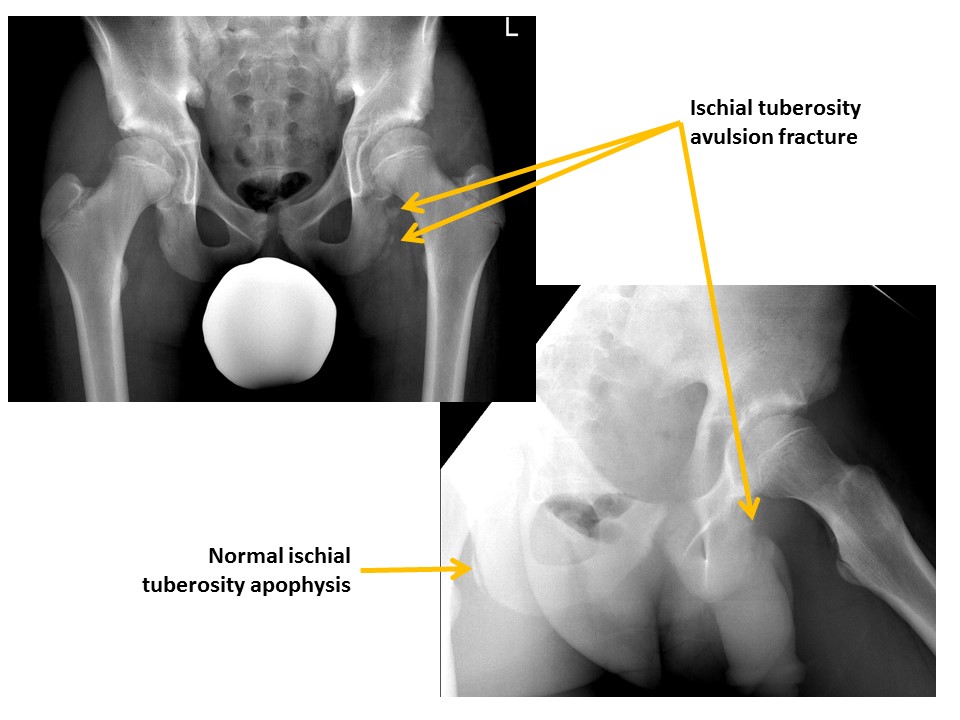

There are avulsion fractures at the ischial tuberosities. [Yes/No]

Ischial spine avulsion fractures are present. [Yes/No]